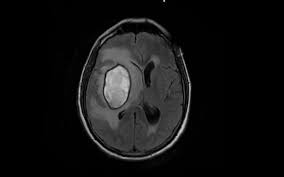

Empty Sella With Enlarged Basal Cisterns Flow Void In Aqueduct Csf Congestion Etiology Congestion Cistern B Rain